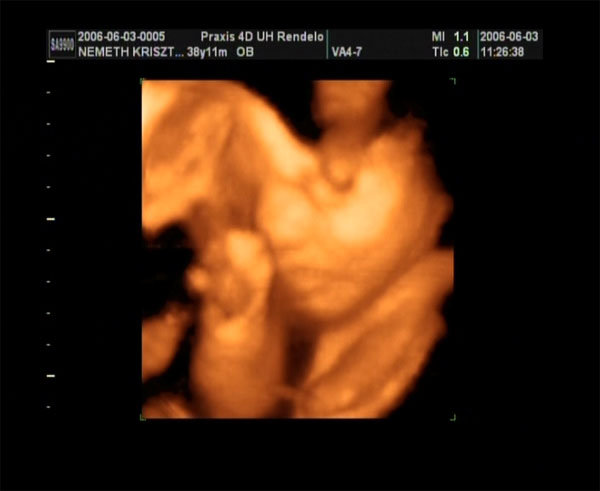

Hétfőn megyek dokihoz és szerdán megyünk 4D-re :) Ismét sűrű hetünk lesz, nem beszélve arról, hogy a házi dokimhoz is el kellene menjek, hogy kiírjon ismét táppénzre mert megint ki fogja találni, hogy nem szóltam időben...